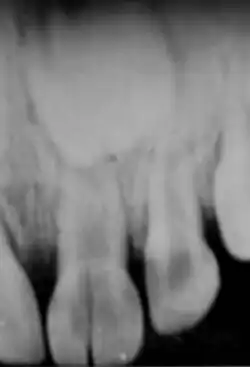

Intrusion

II s'agit du déplacement de la dent dans son alvéole souvent accompagné de fracture alvéolaire. Signes cliniques : la dent est plus courte voire invisible (attention que la dent soit toujours là), il y a une douleur spontanée et un son métallique à la percussion de la dent.